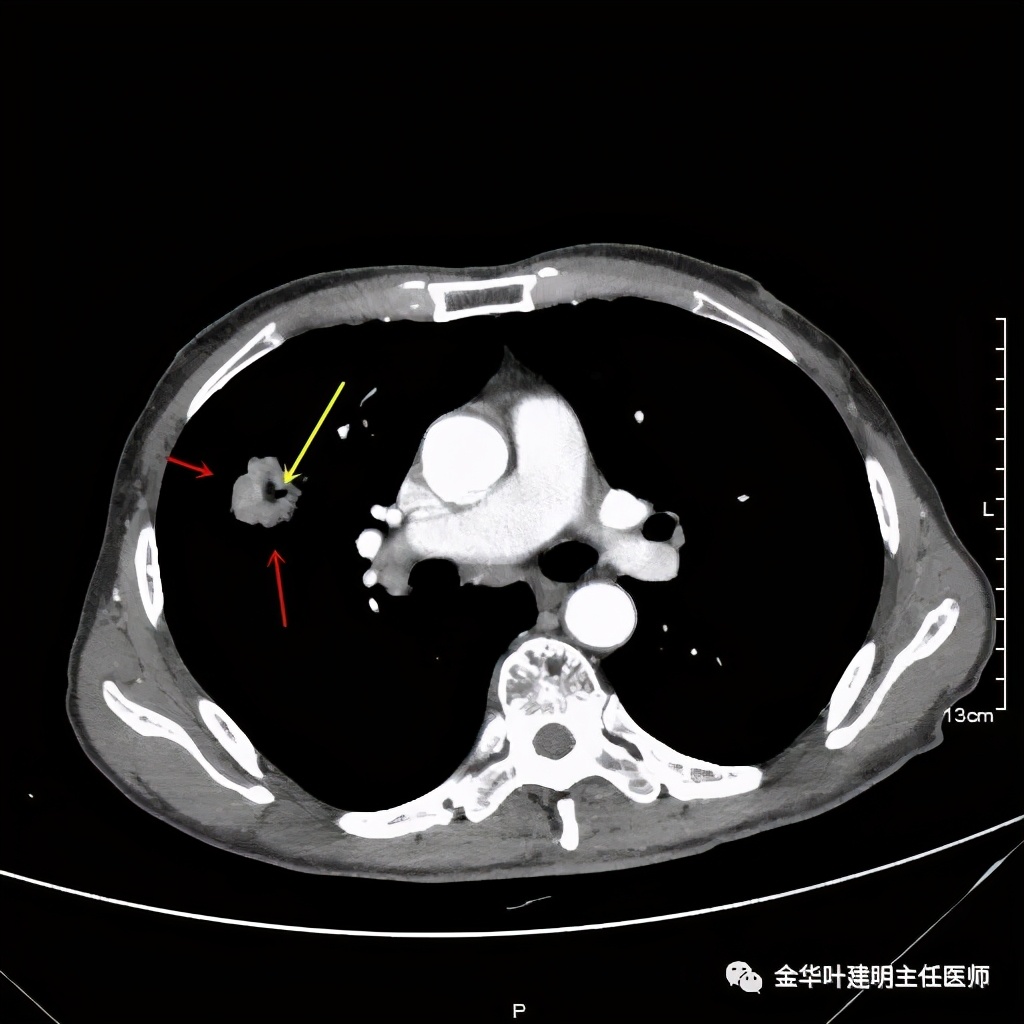

上图紫色箭头示明显的叶间胸膜牵拉,红色箭头示病灶,中间还有空腔,边缘有细毛刺,感觉上病灶就是有收缩力而僵硬的

上图示病灶内部有条索状的强化影,考虑是病灶内的新生血管可能性大

上图示病灶强化不等,表现不平,中间有空洞,空洞旁边有偏低密度区(坏死?)

上图示病灶膨胀分叶,表面不平,像个土豆

上图示病灶密度不均,有偏低密度的区域

上图黄色箭头示空洞形成,病灶表面不平

从影像的细节上看,有许多的影像表现是恶性的征象,这样的病灶我是认为必定恶性的,即使肺穿刺阴性!应该是假阴性,或者说,肺穿刺活检阴性并不足以让我认为它可排除肺癌,而是高度怀疑该阴性是假阴性。仍强烈建议手术切除,可以直接做肺叶切除并清扫淋巴结。患方接受了我的建议,头天刚办理出院的,次日又到我们科办理了住院手续。完善相关检查后,我们很快为其进行了“单孔胸腔镜下右上叶切除及淋巴结清扫术”,手术顺利,术后大体肉眼看就是典型的肺癌,中间坏死空洞,肿瘤质硬,收缩力强,表面不平,切面鱼肉样。术后病理确认是浸润性腺癌,下面是石蜡病理报告: